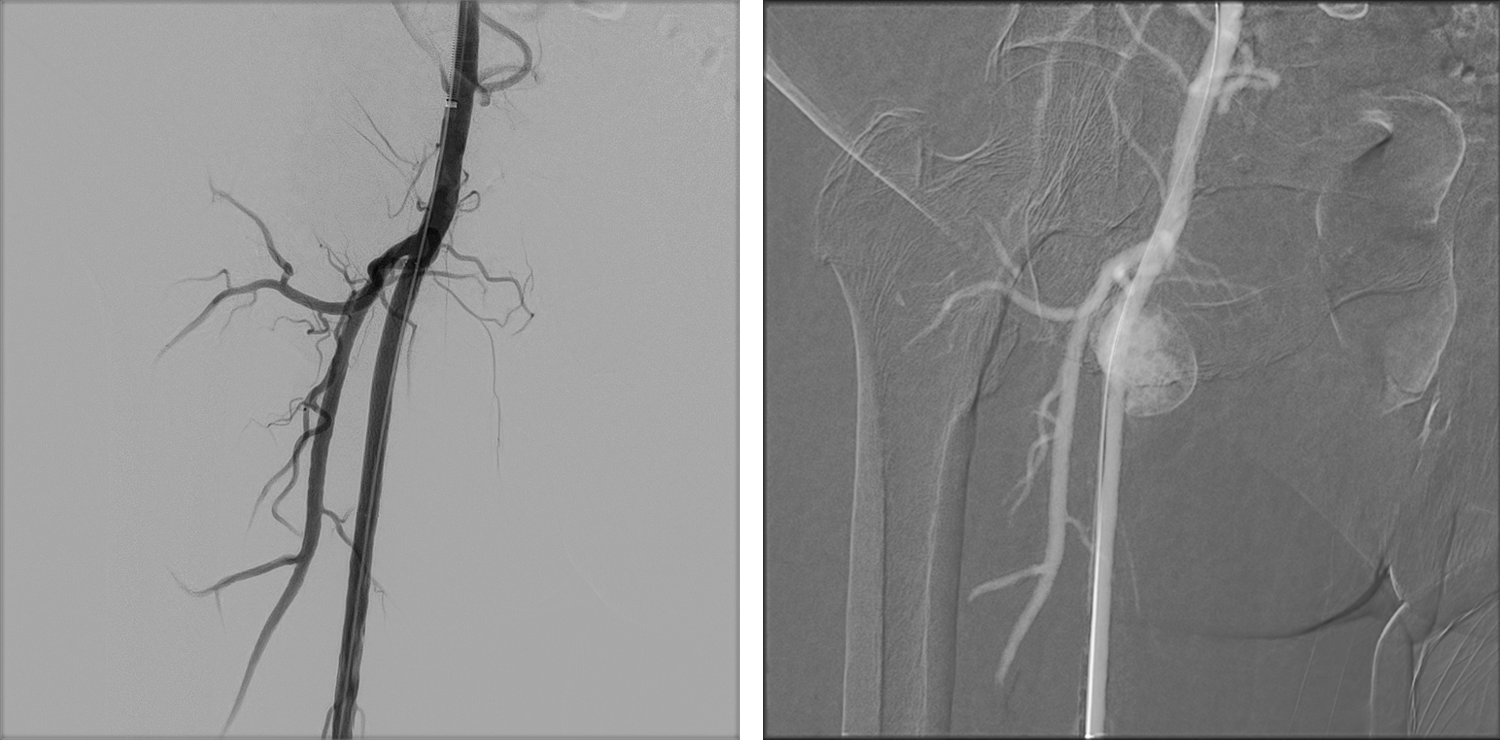

Image of the Week - 19 February 2025

Doctor Nassima EL KARROUMI

Mrs Kenza Alami

Professor Najat Mouine